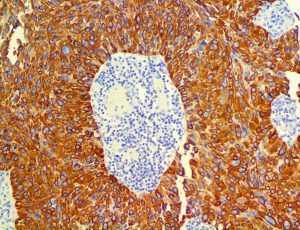

The first cytokines released are interleukin 1β (IL-1β) and tumor necrosis factor-α (TNF-α), which attract a variety of circulating white blood cells (WBCs) to the infection site, including neutrophils, monocytes, macrophages, and natural killer (NK) cells. This response, along with the antipathogenic chemicals released by these cells (i.e., complement), comprise the innate immune response. These cells directly attack the invading pathogen and also release additional cytokines, chief among them interleukin-1 and 6 (IL-6). IL-6 is essential for invoking the adaptive immune response, which calls T-cells, B-cells, and T helper (Th) cells to the infection site. IL-6 also stimulates further recruitment, proliferation and activation of macrophages.

This activation induces inflammatory monocytes to highly express IL-6, starting a localized and then systemic cascade effect that results in hyperproduction of IL-6, which accelerates the inflammatory process. Because IL-6 also increases vascular permeability, excessive levels cause blood vessels to become very leaky. This, along with clotting factors released from vascular endothelial cells, stimulates the coagulation cascade, resulting in microthrombosis (tiny clots), which leads to ischemia and tissue death of the kidney, intestines, heart, liver, brain and extremities.